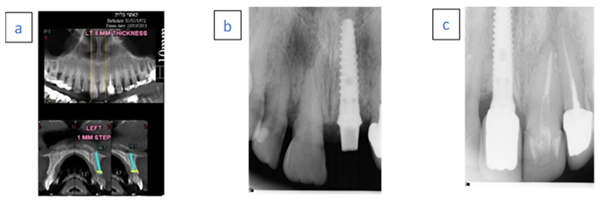

- A 65-year-old female patient.

- Nonsmoker with chronic advanced periodontitis.

- Case 1 (a) A hopeless second right premolar due to vertical root fracture.

- Case 1 (b) Immediate implant placement with temporary abutment.

- Case1 (c) Follow-up examination after 38 months.

- A 56-year-old male patient.

- Case 2 (a) A hopeless left maxillary first premolar tooth due to vertical fracture.

- Case 2 (b) Immediate implant placement with temporary abutment. Radiopaque material demonstrated above the implant neck.

- Case 2 (c) Follow-up examination after 36 months.

- A 46-year-old female.

- Nonsmoker with generalized aggressive periodontitis.

- Case 3 (a) Hopeless left central incisor due to advanced bone loss.

- Case 3 (b) Immediate implant placement with temporary abutment. Radiopaque material demonstrated above the implant neck.

- Case 3 (c) Follow-up examination after 96 months.

- A 76-year-old female.

- Case 4 (a) Hopeless left lateral first incisor due to external root resorption.

- Case 4 (b) Immediate implant placement with temporary abutment.

- Case 4 (c) Follow-up examination after 24 months.